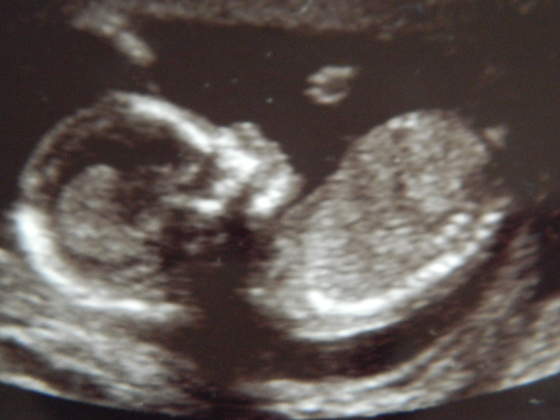

Kruszki, piękne zdjęciaA znacie płeć? Bo mi na dziewczynkę wygląda - tak po twarzy

hehehe no to zescie teraz napisalykruszki piękne małe słoneczko, a mnie na chłopczyka wyglądahihi

...w końcu dowiemy się wszystkie kto mieszka w naszych brzuchach... :-)